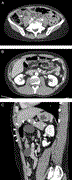

Paraganglioma or pheochromocytoma? A peculiar diagnosis

Ricardo Rodrigues Marques and others

Journal of Surgical Case Reports, Volume 2018, Issue 4, April 2018, rjy060, https://doi.org/10.1093/jscr/rjy060